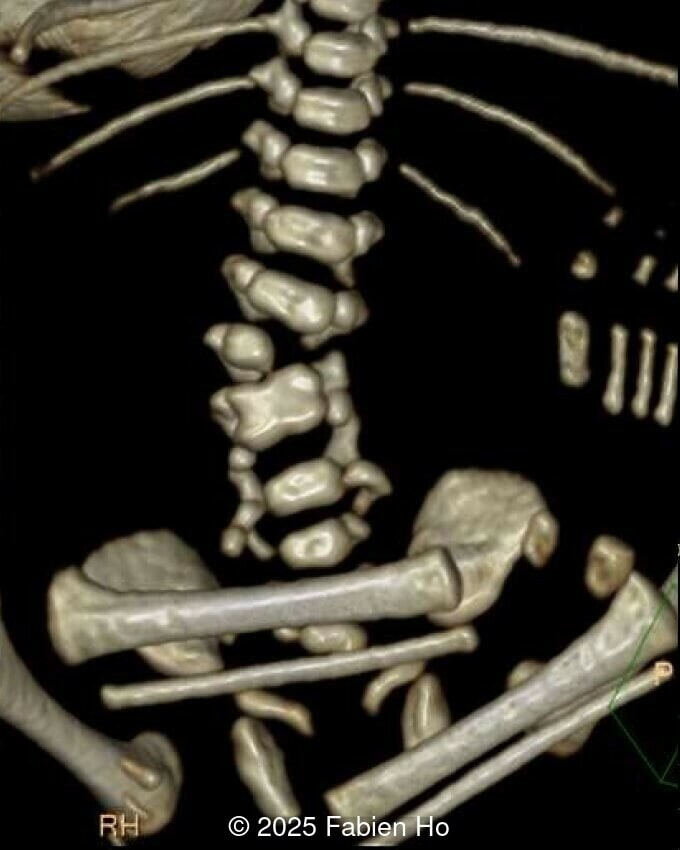

At 36 weeks gestation, the abdominal findings were unchanged however, the bones appeared short (<1st percentile) and the spine had an unusual appearance, therefore a computed tomography was performed at 37 weeks gestation.

Our prenatal ultrasound revealed a male fetus with megabladder, dilation of both ureter and kidneys, and thinned kidney parenchyma consistent with Lower Urinary Tract Obstruction (LUTO). Additional findings suspected on ultrasound and confirmed on computed tomography included:

- Short long bones (<1st percentile), normal mineralization, and no sign of lethal chondrodysplasia

- Evidence of Potter's sequence due to the lower urinary tract obstruction with small thorax compared to the abdomen, hyperextended neck, and pes varus.

- Dysostosis: Hemivertebrae L3, fused L4-L5, abnormal left foot with short metatarsals and missing phalanges